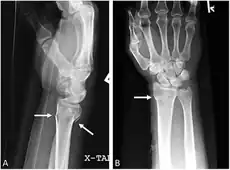

-

Bilateral Colles fractures/frontal -

Bilateral Colles fractures/lateral -

Colles fracture